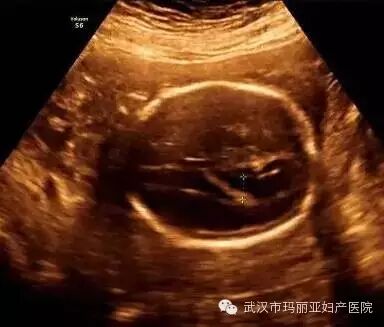

武汉玛丽亚妇产医院引进的世界领先的美国GE-E8四维彩超设备室目前世界上最先进、分辨率最高的彩色超声设备,具有即时立体成像、清晰准确的特点。

它能够多方位、多角度地观察宫内胎儿的生长发育情况,为早期诊断胎儿先天性体表畸形和发育异常提供科学依据。还能对胎儿的体表进行检查,如唇裂、脊柱裂、大脑、肾、 骨骼发育不良等,以便尽早的进行治疗。

玛丽亚美国GE-E8四维彩超排畸成功案例